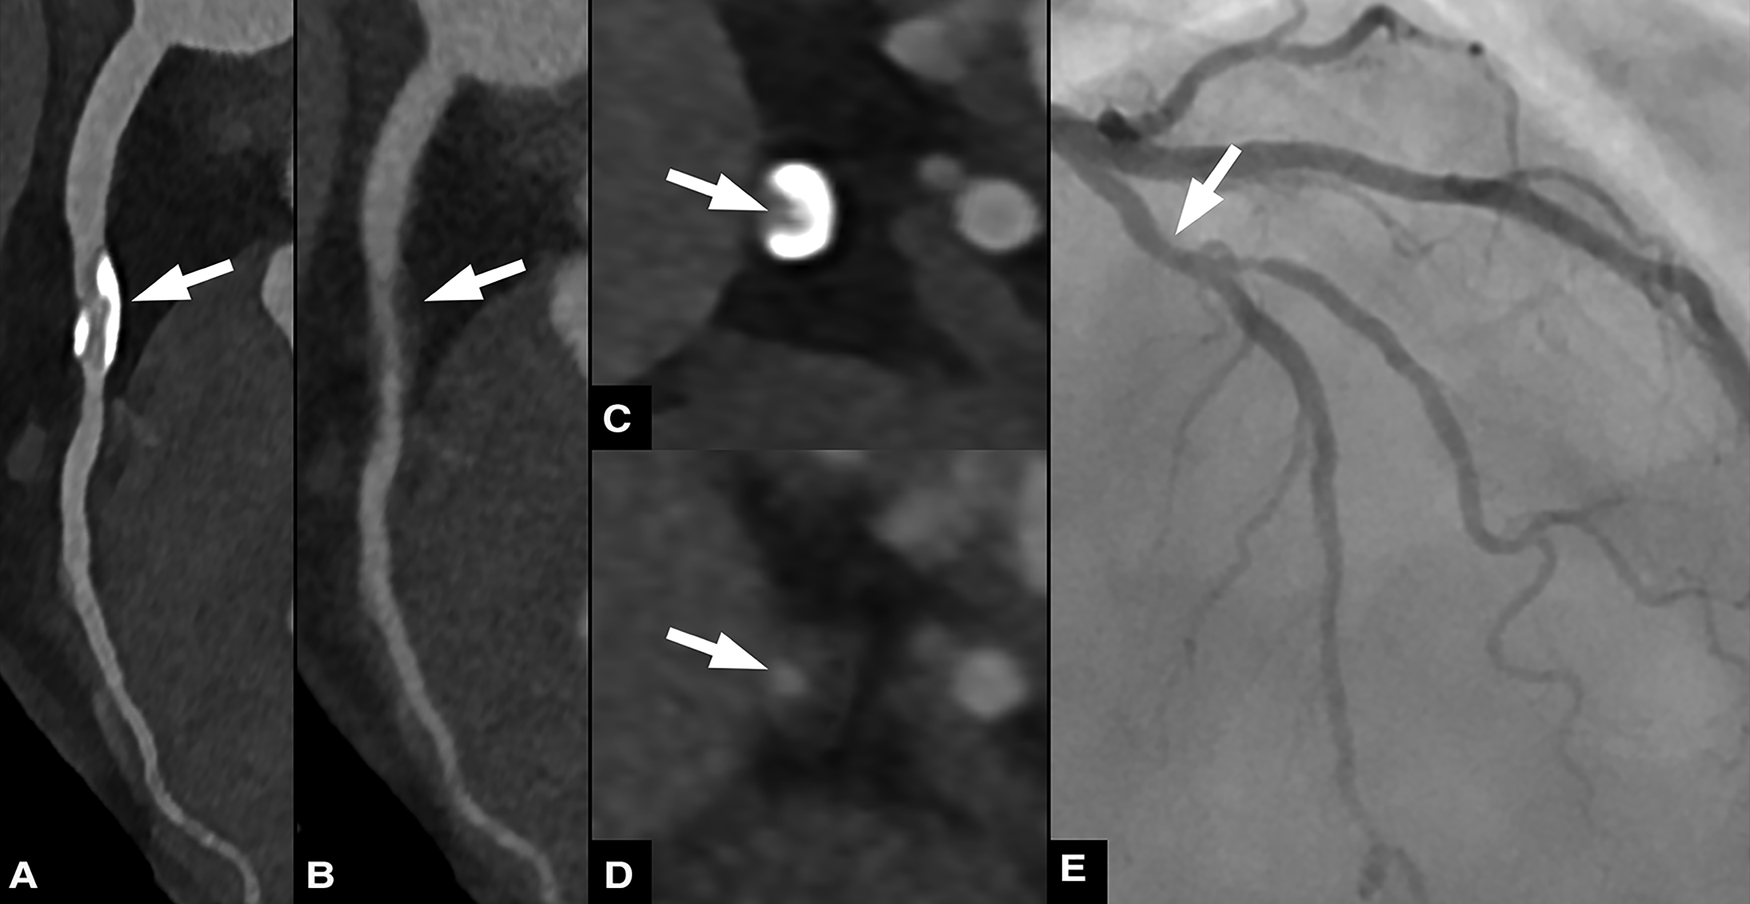

Figure 4

Sixty three-year-old male patient with chronic coronary syndrome. Curved planar reformations of conventional (A) and virtual non-calcium (VNCa) images (B) show calcified and subtracted calcified plaques, respectively, in the proximal left anterior descending artery (LAD). Corresponding axial images show the calcified plaque (C) and the vessel lumen after subtraction (arrow) (D) invasive coronary angiography (E) confirmed the presence of a moderate stenosis in the proximal LAD.